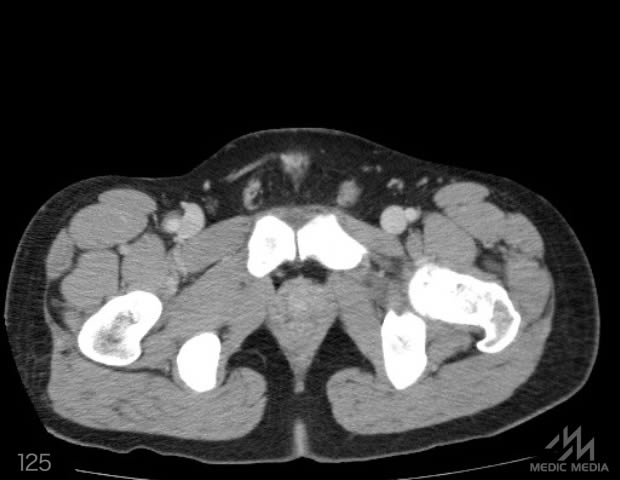

造影CT

スライド(画像下)を動かしながら,CTで臓器の位置を確認してみましょう.

消化器